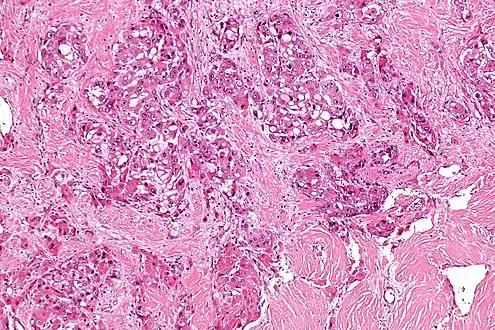

Micrograph of fibrolamellar hepatocarcinoma showing the characteristic laminated fibrosis between the tumor cells with a low NC ratio. H&E stain.

The histopathology of FLC is characterized by laminated fibrous layers, interspersed between the tumor cells. Cytologically, the tumor cells have a low nuclear to cytoplasmic ratio with abundant eosinophilic cytoplasm.[1] Tumors are non-encapsulated, but well circumscribed, when compared to conventional HCC (which typically has an invasive border).